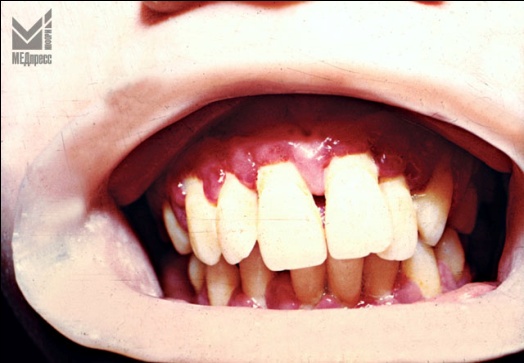

| Рис. 1. и 2. Десневой край и десневые сосочки отечны, рыхлые, имеют цианотичный оттенок. Имеются пародонтальные карманы с выбухающими грануляциями и гнойным отделяемым. Отложения зубного камня. Оголение корней зубов. Зубы подвижны. (14 и 16 лет). |